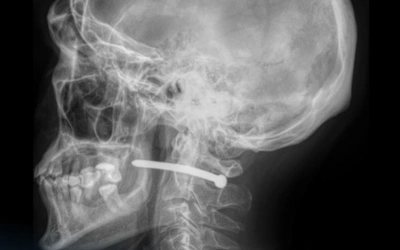

Петропавл қалалық көпбейінді аурухананың мәліметінше, рентгендік зерттеуден кейін пневматикалық пистолетпен атылған шегенің ер адамның құлағының маңына кіріп, мойын омыртқасы жанынан өткені белгілі болды.

Дәрігерлердің айтуынша, маңызды мүшелердің зақымдануына сәл ғана қалған екен.

Жақ-бет хирургтері шегені алып, тиісті ем-дом жасады. Кейін жараны тігіп, науқасты бірқатар ұсыныммен үйге жіберді.